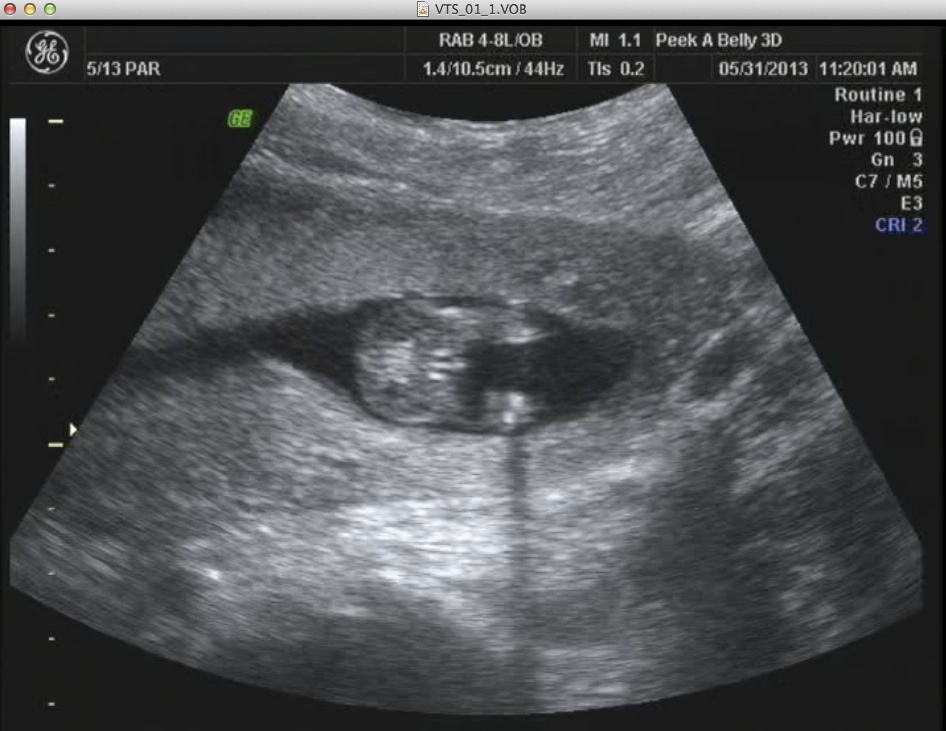

14 week u/s pointed to boy, 20 week u/s leaning towards girl. . . .need another opinion here. :-)

I had a funsies ultrasound in Illinois and was led to believe that my little one was a boy, which fell in line with my thoughts and feelings. However, I had the anatomy scan at 20 weeks and the tech said that she was "pretty sure" then "99.9" sure that it was a little girl.